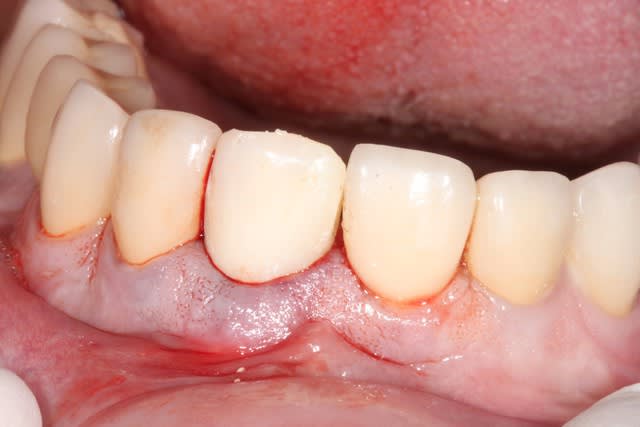

photo de controle vue vestibulaire et occlusale 8 mois post chir

puis à 2 ans post op

on constate que contrairement à la 11 surlaquelle il y a un affaissement de l'os vestibulaire

sur la 21 le volume est préservé

Si je peux me permettre, la 11 semble plus naturelle, car le zénith gingival est plus ovoide. La 21 possède certe plus de volume de tissu en vestibulaire, mais le collet gingivale est trop coronaire, effet de dent trapue.